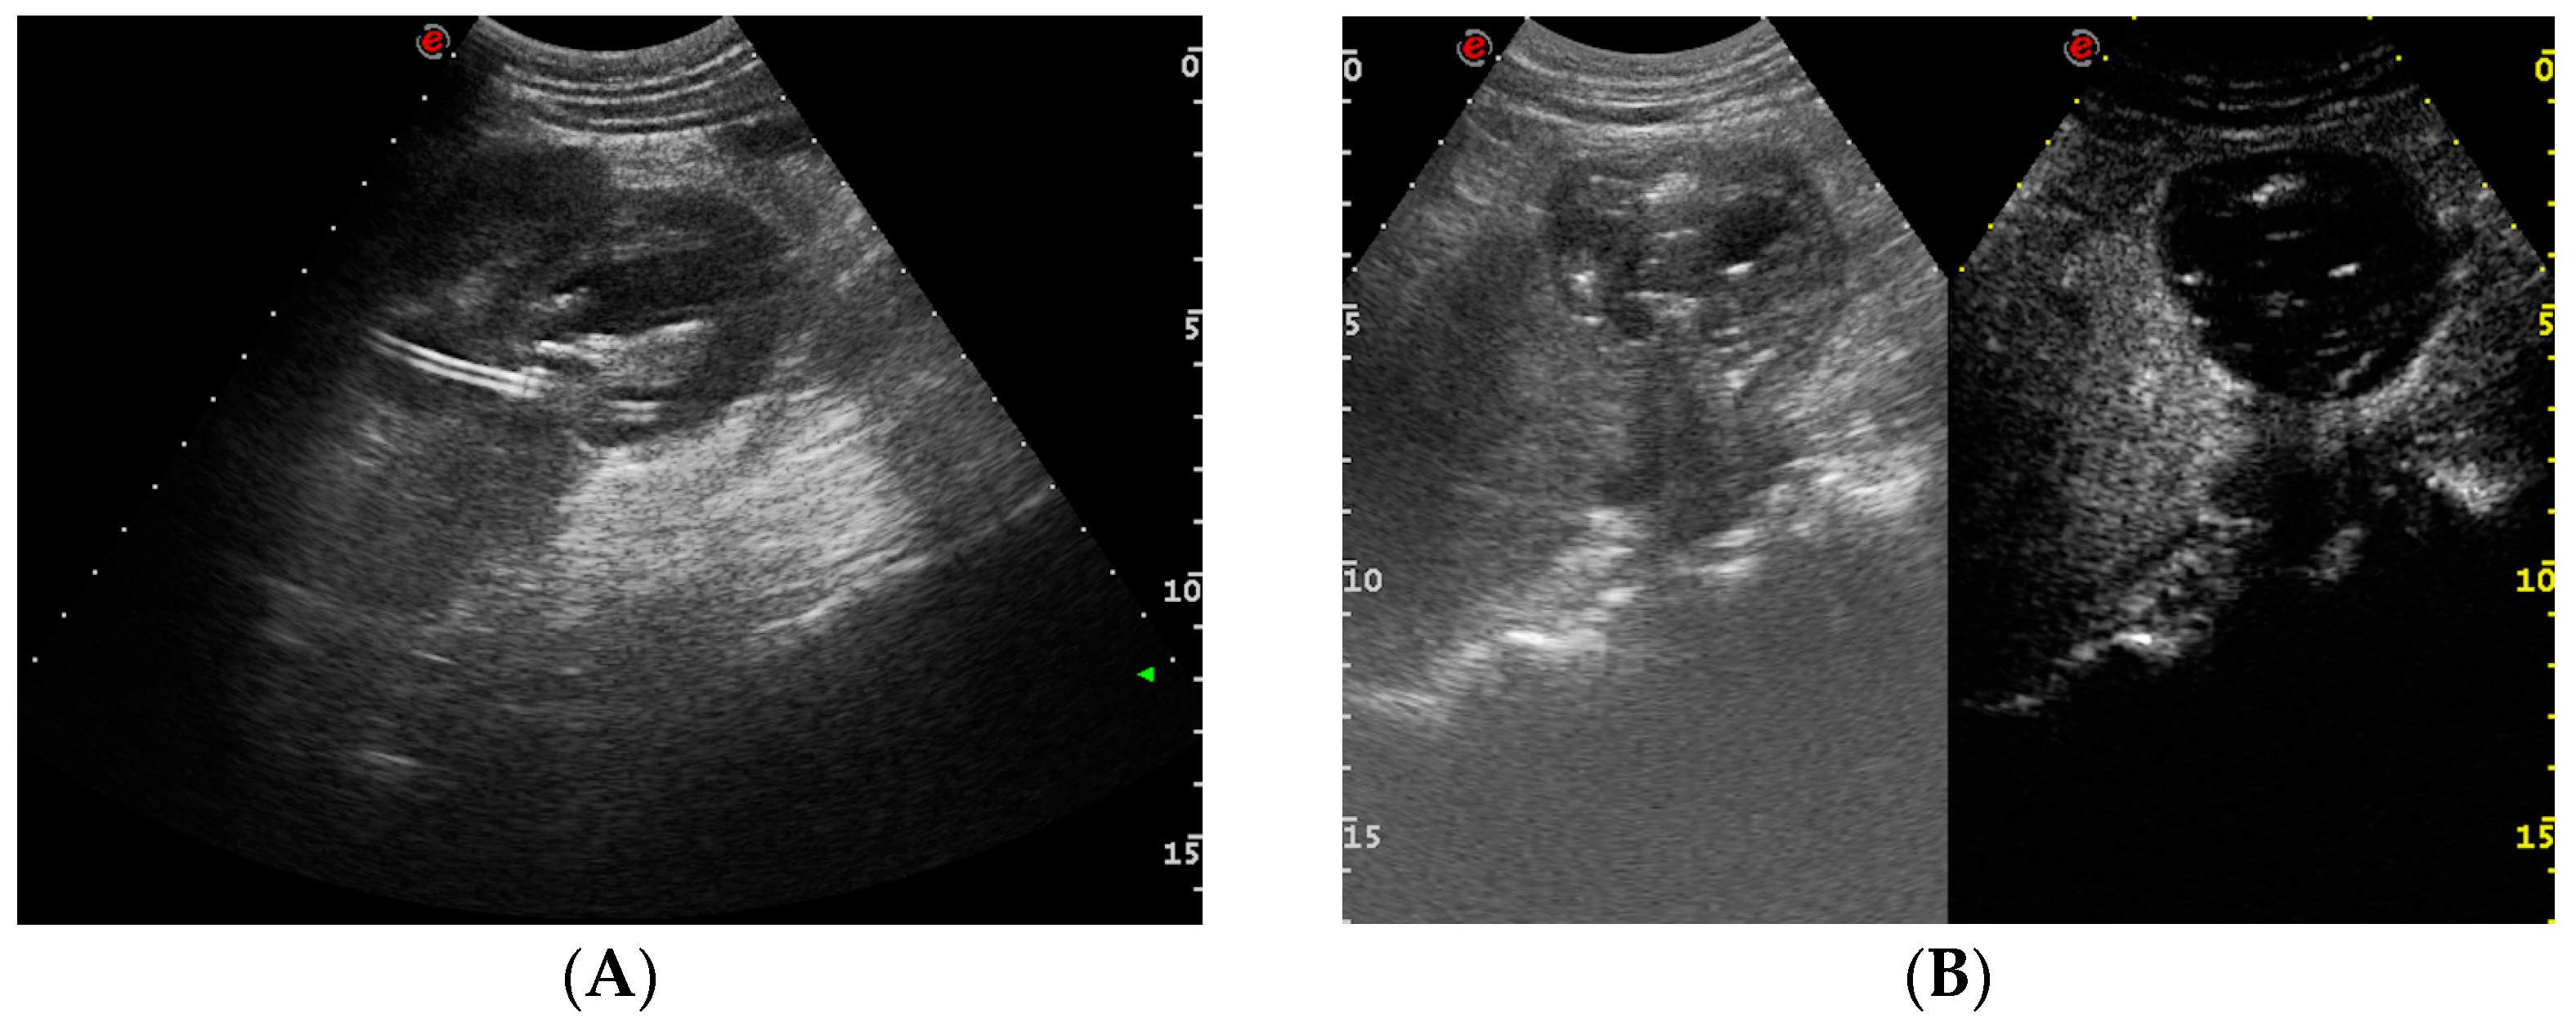

- Urinary tract infection: Stent colonization by bacteria, with an overall incidence ranging from 42% to 90%, is a significant clinical challenge that can lead to a urinary tract infection. In some instances, this infection can result in complications, such as acute pyelonephritis (Figure 8) and renal failure [31,32]. For most patients experiencing a ureteral obstruction, stent placement is carried out with antibiotic prophylaxis, typically administered as a single dose concurrent with the procedure. In cases where a urinary tract infection is already known, the insertion of the stent should be delayed whenever possible until the appropriate treatment with culture-specific antibiotics allows for urine sterilization [32]. US serves as the first-line diagnostic tool to assess the urinary tract in patients presenting with the symptoms of pyelonephritis. Unfortunately, pyelonephritis lacks clear gray-scale findings useful during characterization [33]. Consequently, most patients with clinically suspected pyelonephritis have negative results from US. In cases where imaging is deemed necessary, CT emerges as the preferred modality, providing comprehensive anatomical and physiological information and accurately delineating both intra- and extra-renal pathological conditions. The presence of urinary tract gas, calculi, hemorrhage, renal enlargement, inflammatory masses, and obstruction can be easily detected by CT. Specifically, the affected regions may show a lower attenuation due to edema with pockets of higher attenuation representing the foci of hemorrhage. However, these findings are frequently absent, and unenhanced CT images may appear normal. It is only after the administration of contrast material that the diagnostic features of pyelonephritis become evident. In advanced stages, sepsis is a potential complication, occasionally presenting a critical issue in a debilitated cancer patient. The close monitoring of the patients after the procedure is imperative, with a heightened awareness of the potential for sepsis. The incidence of sepsis following catheter insertion varies between 1.5% and 7%, particularly in patients with pyelonephritis [1,2].